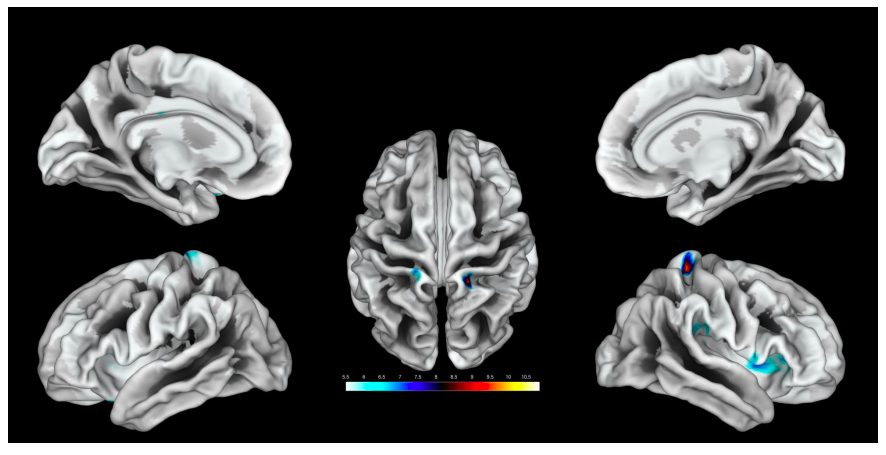

El estudio se llevó a cabo con la participación de 20 mujeres adultas, a las que se les estimuló la región del clítoris con los dedos y se identificaron activaciones en ambos lados de las áreas dorsolaterales, en alineación con la ubicación anatómica del órgano.